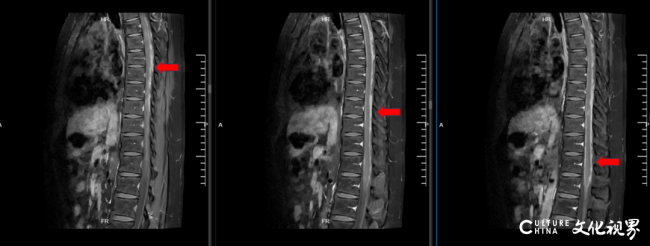

患者术后26月,MR全脊柱平扫+强化(颈胸腰)

2025年10月29日,患者术后33月,用药后2月,MR全脊柱平扫+强化(颈胸腰):原T9-T12椎体水平脊髓转移病灶强化明显减轻,未见新发病灶,腰椎转移灶强化几乎消失,临床症状显著改善。